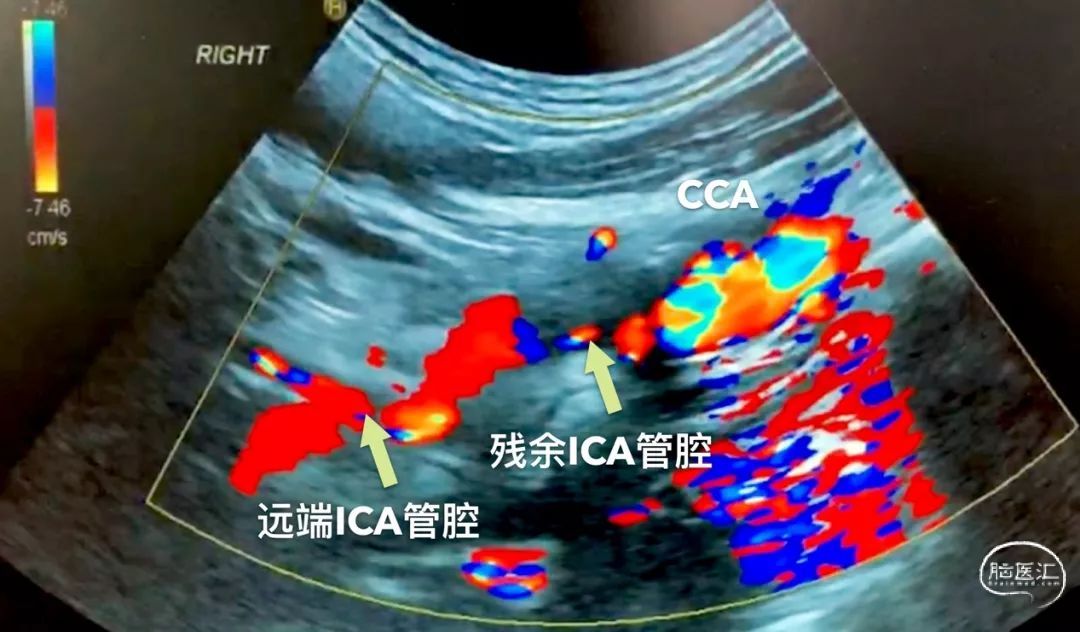

恰好我那天有点空闲,惬意地看同志们忙碌![]() ,随即大家观点一拍即合——急诊复合手术再通。也许是运气好,都是新鲜血栓,返向血流就可以把新鲜血栓推挤出来,随后马上联系手术室,连夜手术!血管超声的美女闻讯而来,弱弱的抛来一句“是闭塞,但闭塞远端通畅,有一支小血管供血”,这是什么道理?ICA颈段的分支?

,随即大家观点一拍即合——急诊复合手术再通。也许是运气好,都是新鲜血栓,返向血流就可以把新鲜血栓推挤出来,随后马上联系手术室,连夜手术!血管超声的美女闻讯而来,弱弱的抛来一句“是闭塞,但闭塞远端通畅,有一支小血管供血”,这是什么道理?ICA颈段的分支?

对于超声的结果,我有些迟疑是否要进行急诊手术。再次复查DSA,结果真的是那样一支小动脉啊![]() ,从椎动脉肌支吻合到这个分支,向下进入ICA起始段不远处,再逆行向上供应整个ICA。

,从椎动脉肌支吻合到这个分支,向下进入ICA起始段不远处,再逆行向上供应整个ICA。